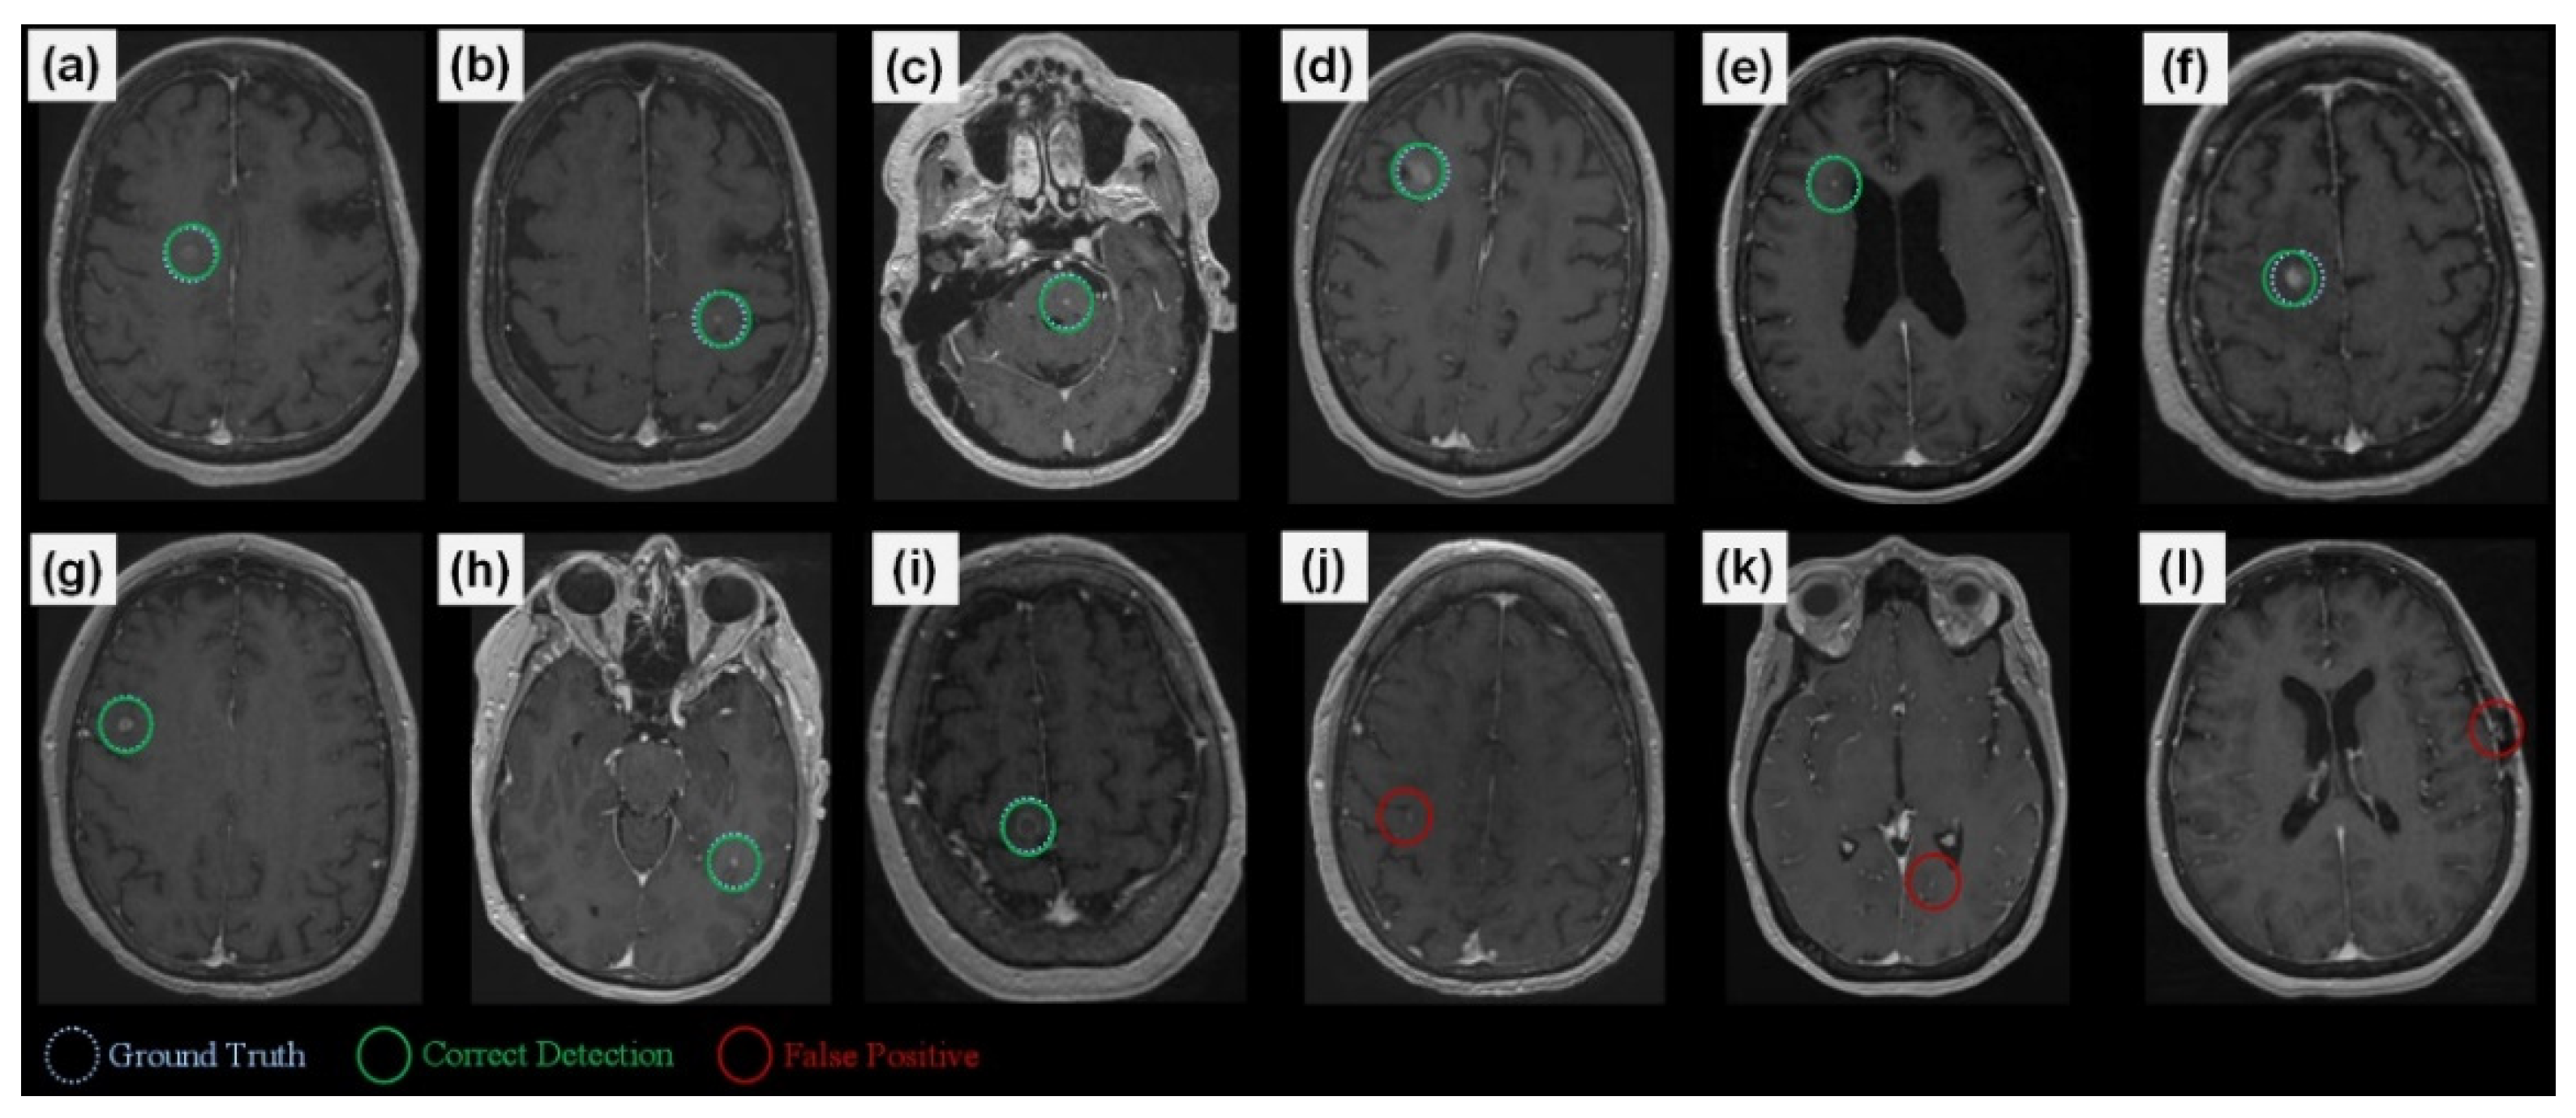

3.1. Validation Study

3.2. Experiments with System Parameters

3.2.1. Teacher Model Sensitivity